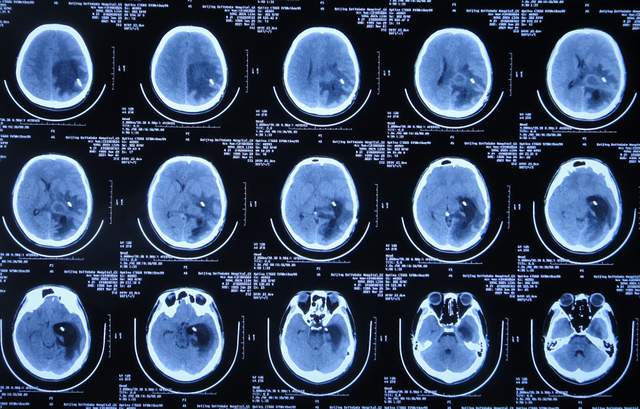

左颞角脑室腹壁外引流术后21天即2021年3月1日,查头颅CT示颞角仍有扩张(图-17)。

图-17:2021年3月1日头颅CT

左颞角脑室腹壁外引流术后23天即2021年3月3日,头颅CT增强和核磁增强示有脑脓肿(图-18、图-19)。

图-18:2021年3月3日头颅CT增强

图-19:2021年3月3日头颅核磁增强

2021年3月8日(左颞角脑室腹壁外引流术后28天),进行了脑脓肿切除术(图-20)。

图-20:2021年3月8日头颅CT

2021年3月9日(左颞角脑室腹壁外引流术后29天,脑脓肿切除术后次日),查头颅CT示脑脓肿切除术后(图-21)。

图-21:2021年3月9日头颅CT